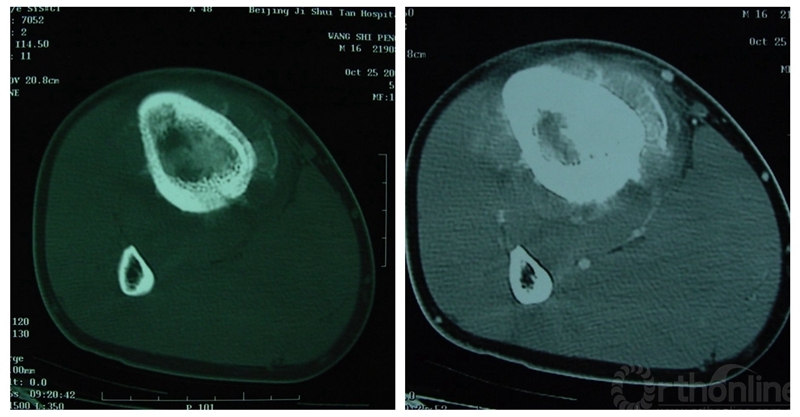

CT扫描可提供更丰富的影像信息。CT用于明确髓内和软组织肿块范围较X线平片敏感,在髓腔内CT值的增高一般提示已有肿瘤的浸润,并能及早发现髓腔内跳跃灶(图2)。CT对骨肉瘤的瘤骨显示优于X线平片和MRI检查,这是由于瘤骨周边部分的骨化弱于中央部分,CT扫描可敏感地分辨较弱成骨的周边部分,MRI常不易区分信号相近的弱成骨区和未成骨区。肺部CT扫描是确认有无肺转移灶的最好方法。

图2. 典型的骨肉瘤CT表现